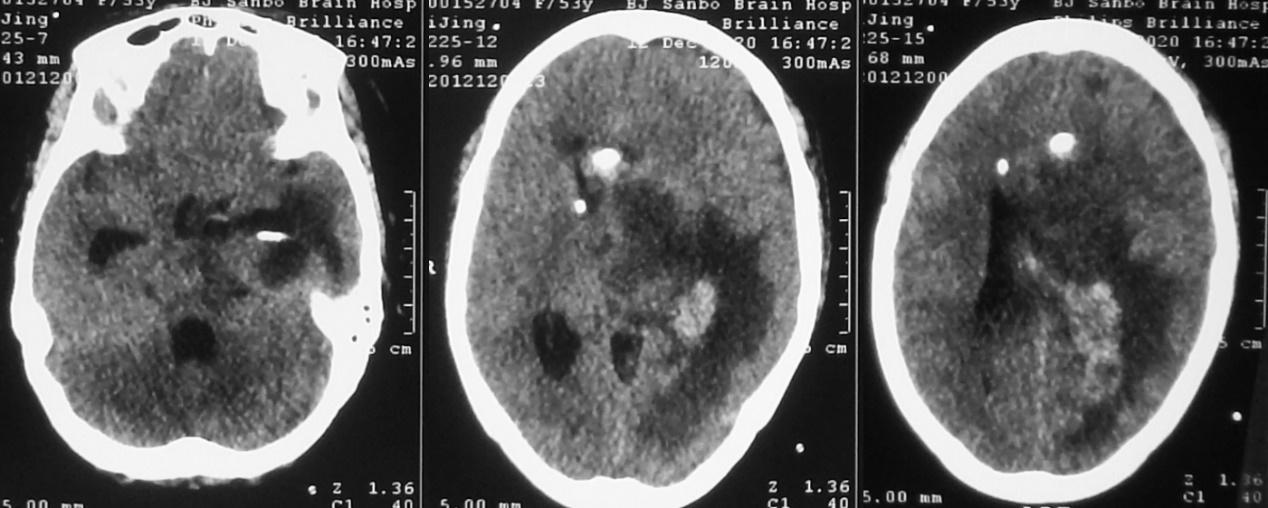

脑室外引流术后第2天即2020年11月22日早上8点,患者好转为清醒,复查头颅CT见左侧脑室缩小( 图-4 );但患者出现发热,引流出的脑脊液浑浊,医生考虑患者丘脑病变为脑脓肿,给予头孢曲松抗炎治疗。

图-4: 2020年11月22日头CT

但当天晚上21:00,意识再次变差为嗜睡,复查头颅CT见脑室扩张( 图-5 ),考虑脑室引流不通畅,给予调整引流管后引流好转。

图-5: 2020年11月22日晚上头CT